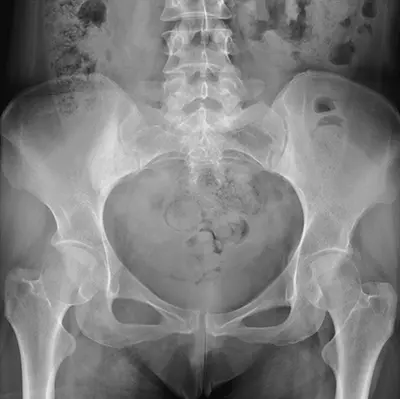

To understand what a labral tear is, it helps to first review how the hip joint works. The hip is a ball-and-socket joint, formed by the femoral head (the “ball”) and the acetabulum (the “socket”) of the pelvis. These two structures move together to allow a wide range of motion during activities like walking or running.

Diagnosing a labral tear requires a combination of medical history, physical examination, and advanced imaging, including:

- X-rays to detect fractures or structural abnormalities.